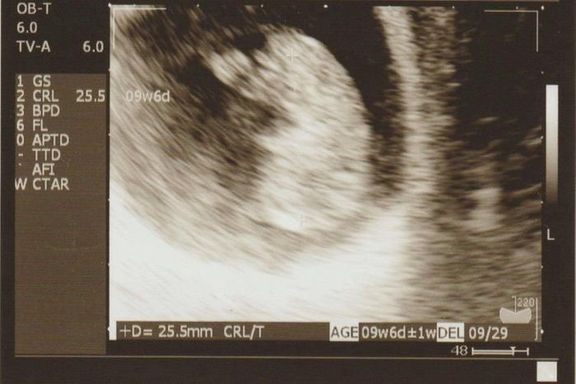

命の始まりは神秘的!2D・3D・4Dのエコー写真で見る「私と赤ちゃんの実録260日」 -

"おなかの中はどうなっていくの? エコー写真で振り返る、高齢ママのはじめての妊娠生活" -